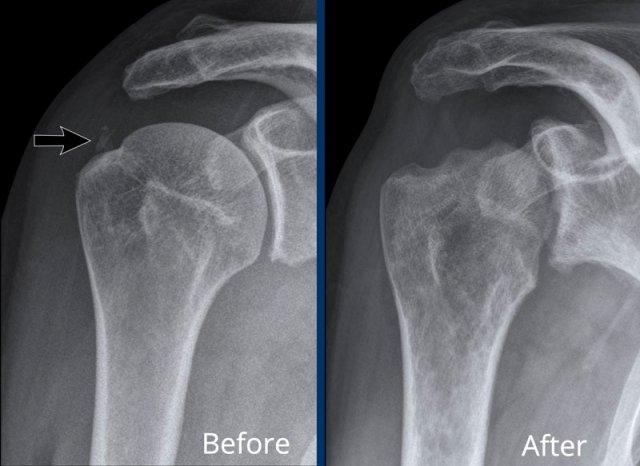

A. Vôi hóa mô mềm tại chóp xoay. Bệnh nhân được tiêm dưới mỏm cùng vai để giảm triệu chứng.

B. Sau tiêm corticosteroid, xuất hiện mất sụn khớp nặng tại khớp ổ chảo-cánh tay và phá hủy xương đầu trên xương cánh tay. Đây là hậu quả của viêm khớp nhiễm khuẩn, một biến chứng hiếm gặp của tiêm khớp.